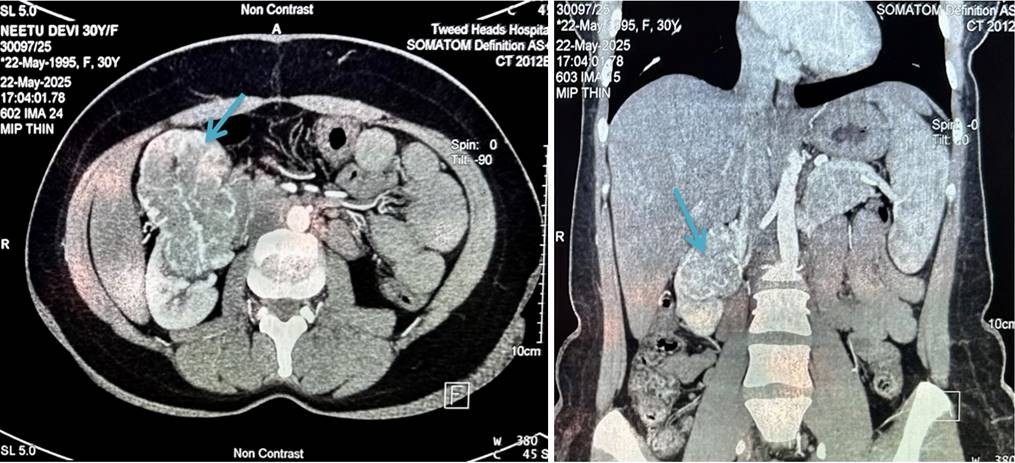

Further radiological investigations were done to find the nature and extent of the lesion in the kidney. Contrast enhanced CT scan showed the exophytic mass to be arising from the anterior mid pole of the right kidney, significantly extending anteriorly with loss of fat planes with gall bladder, second part of duodenum and adjacent segment V of liver. The findings were suggestive of neoplastic etiology of right kidney (Figure 1).

CT renal angiography was performed which revealed similar radiological findings. Further, areas of necrosis were noted. The mass was seen bulging into the perinephric fat and extending superiorly. However, no extension was seen beyond gerota’s fascia. The mass was indenting the right renal vessels with contact angle of 180 degrees. Right renal vein and IVC were normal. Ipsilateral adrenal gland was also unremarkable (Figure 2).